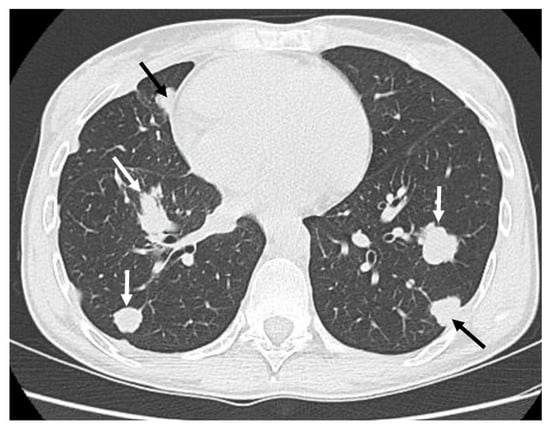

| 26 (F) | Distal tibial diaphysis + Fibula | No | No | Yes (8 months after diagnosis)—Bones, lungs | RT + ChT | DOD |

| 14 (F) | Proximal tibial diaphysis | No | No | Yes (11 months after diagnosis)—Lungs | ChT | DOD |

| 23 (M) | Distal tibial diaphysis | Yes | Yes—Lungs | Yes—Lungs | Cht | DOD |

| 14 (F) | Distal tibial diaphysis | No | No | Yes (18 months after diagnosis)—Lungs | RT | AWD |

| 20 (M) | Mid- and distal tibial diaphysis | No | No | Yes (16 months after diagnosis)—Lungs | ChT | AWD |

| 51 (F) | Mid- and proximal tibial diaphysis | Yes | Yes—Bones, Lymph nodes | Yes—Bones, Lymph nodes, Lungs | ChT | DOD |